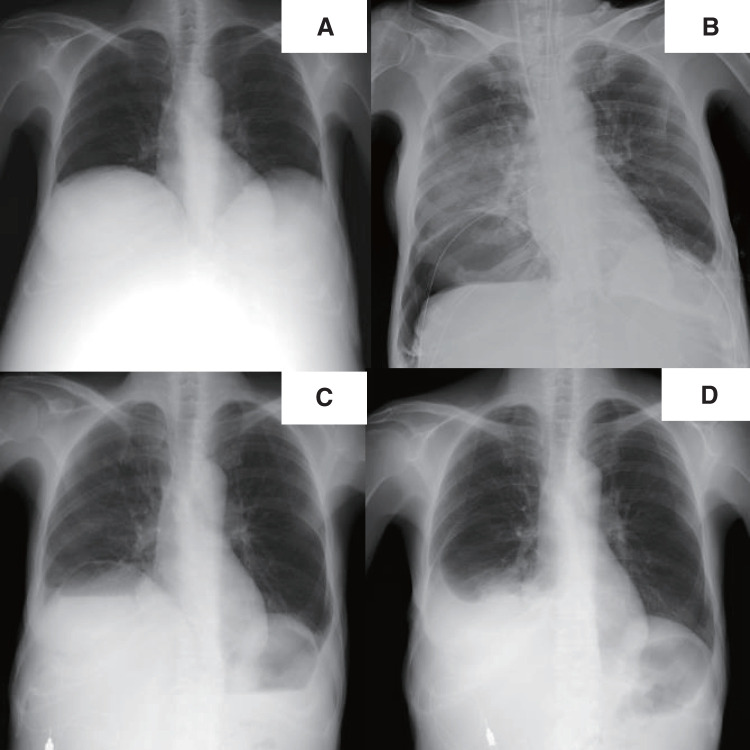

Case presentation: A 57-year-old woman with a diagnosis of autosomal dominant polycystic kidney disease underwent deceased-donor liver transplantation for polycystic liver disease. She did not have any background lung disease, although her right lower lobe was mostly atelectatic due to a remarkably elevated diaphragm. The liver transplant itself was uneventful. A small hole was made in the right diaphragm during the dissection of the liver, but it was successfully repaired without any injury to the lung. On postoperative day 1, the chest radiograph revealed a round hypertranslucency on the right side, which was initially considered subphrenic air retention, and no further evaluation was made at that time. Given that the hypertranslucency persisted, follow-up computed tomography was performed on postoperative day 18, and revealed an air-fluid level above the diaphragm in the right thoracic cavity. Thoracoscopic investigation revealed an intrathoracic hematoma within a pneumatocele in the right lower lobe, which was not detected in the pretransplant computed tomography. The hematoma was removed, and the pneumatocele was resected.